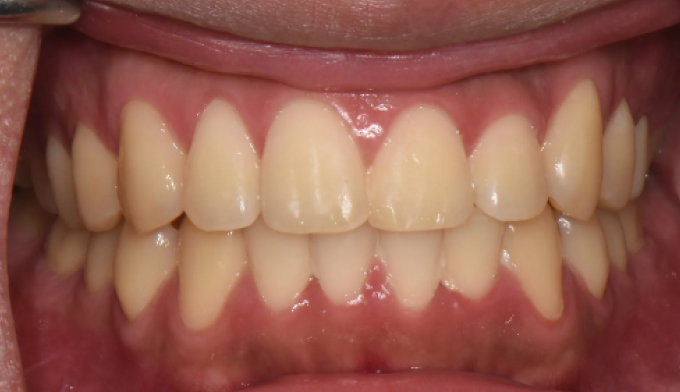

앞니불규칙

앞니를 배열하는데 있어서 필요한 공간이 많지 않은 경우, 전체교정 없이 앞니만 부분적으로 교정하는 방법을 통하여 쉽고 빠르게 치열을 가지런하게 할 수 있습니다. 멀쩡한 앞니를 삭제하고 씌우는 크라운이나 라미네이트 치료를 하지 않아도 됩니다.

교정기간은 7개월 소요되었습니다.